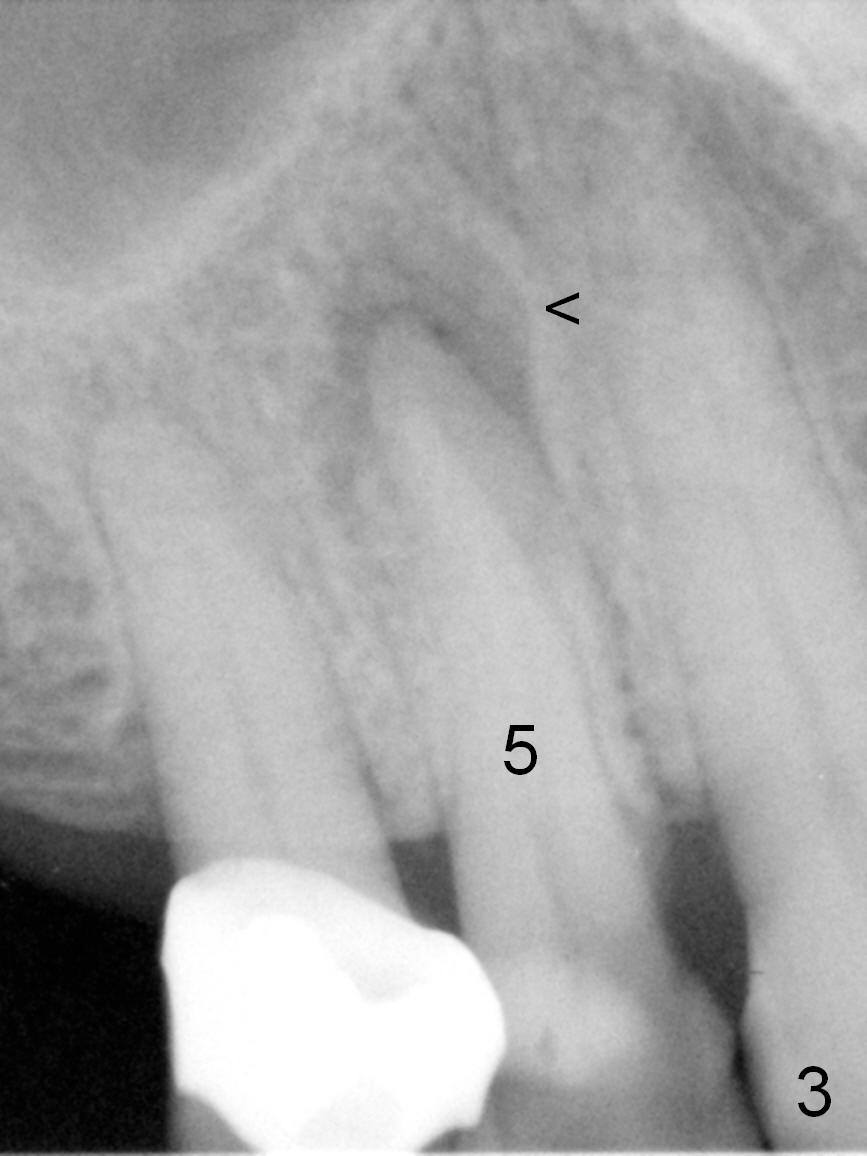

A 72-year-old lady is a bruxer with palatal subgingival fracture of the upper right 1st premolar (Fig.1) with a fistula/periapical radiolucency (Fig.2,3 <).  She insists on saving the tooth, since it is asymptomatic.  Bruxism must be severe, as the canine (Fig.2 ^) is shorter than the lateral incisor.  She has history of #8 fracture and loosening of implant crown at #14.

After long discussion, she agrees with extraction and immediate implant.  After the extraction, granulation tissue is removed.  There is buccal apical fenestration.  The socket is treated with Metronidazole.  The socket depth is 17 mm, while osteotomy depth is 20 mm (Fig.4).  A 4x20 mm tissue-level implant is placed with primary stability (Fig.5,6 I).  A short abutment (A) is placed immediately for an immediate provisional.  The buccal gap is filled with Osteogen plug.  There is no crestal bone loss 3 months postop (Fig.7).  The provisional stays in place with occlusal perforation.  The gingiva is healthy 5.5 months post cementation (Fig.8).